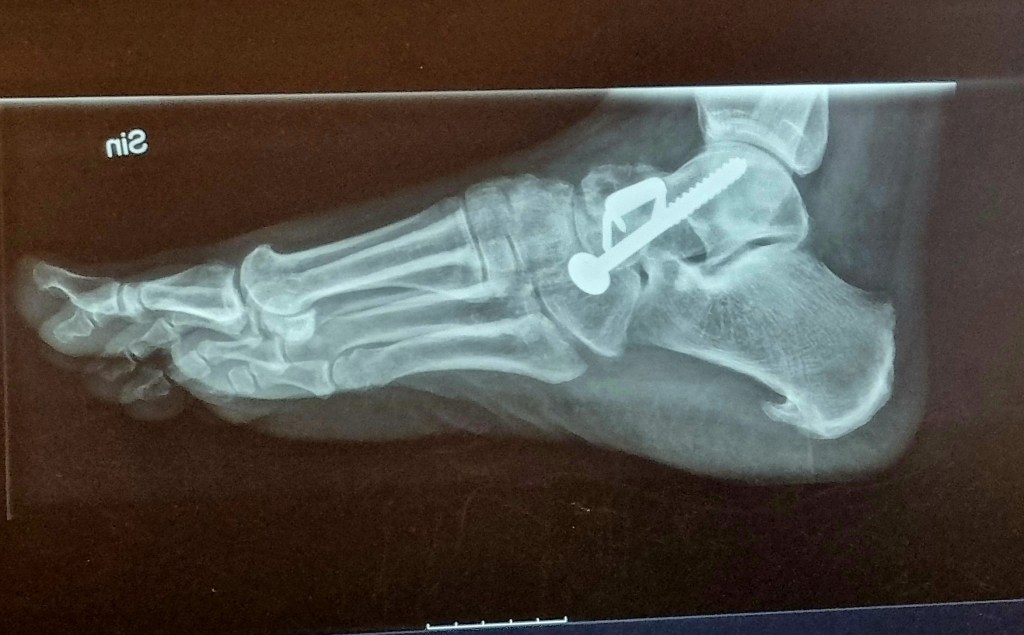

Så, vad ska nu detta handla om förutom fossingarna, jo mina reflektioner kring att ha en fot gipsad. Efter många månader med kraftig smärta i foten så fick jag äntligen komma till ortopeden där en stressfraktur konstaterades. Operationen ägde rum den 13 november-24 och därefter skulle min fot stängas in i tre månader.

Mina första metaller i kroppen, får se om det blir flera under kommande år.